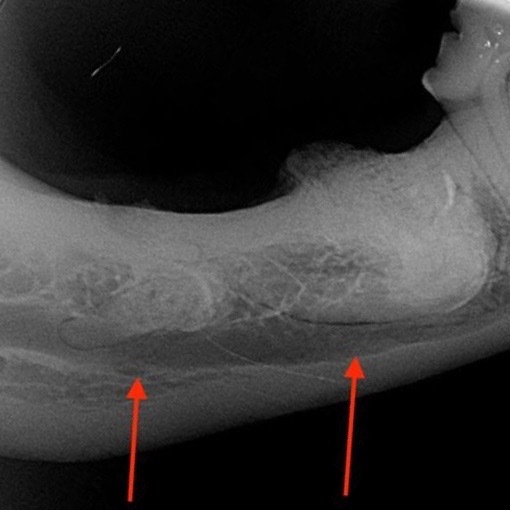

Der hübsche neun Jahre alte schwarze Mischlingsrüde Nando aus Italien wird vorgestellt, da die Besitzerin Zahnstein und einen unangenehmen Geruch aus der Maulhöhle festgestellt hat. Während der Untersuchung werden folgende Befunde erhoben: mittelgradiger Zahnstein an den meisten Zähnen, im Unter- und Oberkiefer je ein abgebrochener Schneidezahn (Abb. 1 und 2) und eine große „Zahnlücke“ im Unterkiefer rechts (Abb. 3). Hier scheinen die drei letzten Backenzähne zu fehlen. Nando ist ein sportlicher und schlanker Hund. Sein Herz schlägt regelmäßig und ohne Nebengeräusche. Dennoch untersuchen wir vor der Operation sein Blut, um mögliche Anästhesierisiken weitgehend ausschließen zu können. Wenige Tage später werden Nandos Zähne in Narkose sorgfältig von Zahnstein befreit und anschließend poliert. Von den beiden abgebrochenen Schneidezähnen und dem Bereich der vermeintlichen Zahnlücke im Unterkiefer werden Röntgenbilder angefertigt. Die Kronen der beiden Schneidezähne sind so tief abgebrochen, dass die Pulpahöhle offen liegt (Abb. 4). Im Bereich der „Zahnlücke“ zeigt das Röntgenbild Wurzelanteile nicht vollständig vorhandener oder vielleicht auch nicht vollständig ausgebildeter Zähne (Abb. 5).

Was bei augenscheinlicher Betrachtung zunächst wie eine ganz normale „Zahnlücke“ aussieht, stellt sich im Röntgenbild ganz anders dar. Bei Nando zeigt es an dieser Stelle Zahnreste, die kreuz und quer im Knochen des Unterkiefers liegen. Nun muss die Entscheidung gefällt werden, ob diese Zahnreste an Ort und Stelle belassen oder operativ entfernt werden. Wir haben die Zahnreste belassen, denn im Röntgenbild sind keine Hinweise auf eine Entzündung der Wurzelanteile oder des sie umgebenden Knochens oder die Ausbildung einer Zyste (s.u.) zu finden. Auch die äußerlich sichtbare Schleimhaut ist in diesem Bereich vollkommen reaktionslos. Nichts deutet auf die in der Tiefe des Unterkieferknochens liegenden Zahnanteile hin. Allerdings muss Nando in Zukunft weiter auf Entzündungs- oder Schmerzanzeichen überwacht werden, denn die Situation könnte sich im Verlaufe seines Lebens noch ändern. Mit zunehmendem Alter wird das jedoch immer unwahrscheinlicher. Eine regelmäßige Röntgenkontrolle zur Evaluierung der tiefliegenden Wurzelanteile ist wünschenswert.

So waren bei Nando sowohl das Alter von neun Jahren als auch die fehlenden klinischen und radiologischen Anzeichen für eine Entzündung bzw. Knochenzyste ausschlaggebend für die Entscheidung, die Wurzelteile an Ort und Stelle zu belassen. Hätten die Röntgenbilder gezeigt, dass sich eine Knochenzyste im Bereich der Wurzelteile ausgebildet hätte, wäre eine operative Entfernung der Zyste und der Wurzelanteile notwendig gewesen. Nando hatte jedoch Glück, ein solch aufwändiger Eingriff war bei ihm nicht notwendig. Er konnte kurze Zeit nach dem Eingriff, von Zahnstein und zwei abgebrochenen Zähnen befreit, wieder nach Hause gehen. Es ist sichergestellt, dass er keine Zahnschmerzen hat und in seiner Maulhöhle keine Voraussetzung für die Entwicklung einer Parodontitis mehr gegeben ist. Wenn die Besitzer seine Zähne täglich bürsten, können sie diesen Status erhalten und gleichzeitig die vermeintliche Zahnlücke im Blick behalten.